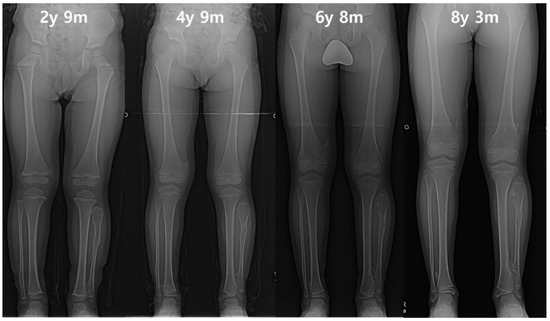

Figure 1. (A) The distance of proximal epiphyses (D) and physes (d) between tibia and fibula. The distance of proximal epiphyses was defined as the gap between the parallel line past the apex of the proximal fibula and the parallel line past the center of the distance between the line across the apex of the tibial spine and the most bottom of the condyle. The distances of proximal physes was defined as the gap between the parallel line passing through the midpoint of the distance between the line across the top of physis; the line crossing the bottom of physis was set as the reference line. (B) The measurement of the ankle joint. The tibiotalar angle was defined as the extension line of the tibial anatomical axis and a line perpendicular to the extension line that touches the dome of the talus. The left lower extremity indicated by the white arrow demonstrates a decreased distal tibiofibular distance compared to the right side, and a prominent ankle valgus deformity is also observed. (C) The tibiofibular synostosis. The white arrow indicates a definite bridge of an exostosis lesion connecting the proximal fibula and tibia without the overlapping cortex.

Figure 4. The serial radiographs of a male patient demonstrated progression of valgus deformity on the left ankle. Despite exostoses in bilateral legs, valgus angulation of the left ankle accompanied by shortening of the fibula was observed, while the neutral alignment was maintained on the right ankle. In the last measurement, the left tibial length was also about 9 mm shorter than the right tibia.